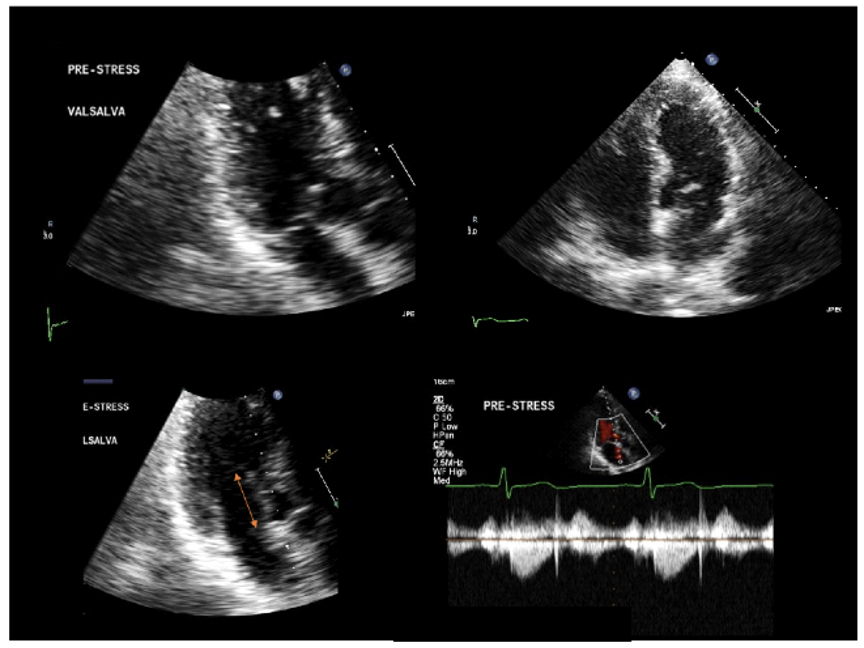

Dr. Harmony G. Reynolds and a research team are proving that OCT and cardiac MRI and can clarify why many women have heart attacks without coronary artery narrowing. Read the interview.